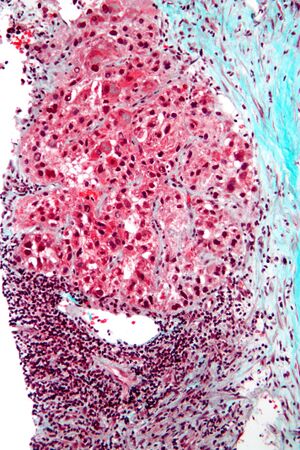

Macroscopically, liver cancer appears as a nodular or infiltrative tumor. The nodular type may be solitary (large mass) or multiple (when developed as a complication of cirrhosis). Tumor nodules are round to oval, gray or green (if the tumor produces bile), well circumscribed but not encapsulated. The diffuse type is poorly circumscribed and infiltrates the portal veins, or the hepatic veins (rarely).[16]

Microscopically, the four architectural and cytological types (patterns) of hepatocellular carcinoma are: fibrolamellar, pseudoglandular (adenoid), pleomorphic (giant cell), and clear cell. In well-differentiated forms, tumor cells resemble hepatocytes, form trabeculae, cords, and nests, and may contain bile pigment in the cytoplasm. In poorly differentiated forms, malignant epithelial cells are discohesive, pleomorphic, anaplastic, and giant. The tumor has a scant stroma and central necrosis because of the poor vascularization.[39] A fifth form – lymphoepithelioma like hepatocellular carcinoma – has also been described.[40][41]